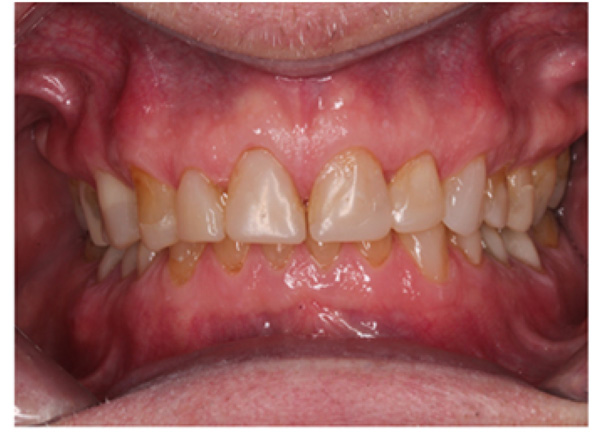

IPS Empress Direct ® (Ivoclar Vivadent, Schaan, Liechtenstein) composite was syringed onto the worn surface and into the stent,which was seated onto the tooth. The composite was cured through the stent for 20 seconds; then the stent was removed, and the composite curing light was used again to ensure afull set for a further 40 seconds. The PTFE tape was removed, the excess composite at the gingival margin was trimmed back with narrow and ultra-fine diamond finishing burs, and a final polish was performed using Shofu Super-Snap Rainbow® discs (Kyoto 605-0983, Japan). The resultsare shown in Figs. (8-10). The slight increase in the vertical dimension is seen when comparing the pre-operative frontal image (Fig. 2) with the post-op image (Fig. 8), where some of the labial surfaces of the lower incisors is now visible, which was planned from the outset.

The occlusal scheme was created using a mutually protected occlusion with canine guidance. The patient was informed of possible transitory problems, including difficulty in eating or speaking and other possible discomforts. He was reassured that adaptation is usually quick. Alower bilaminar (dual-laminate) night guardof 3mm thickness was provided in order toprotect the composites during bruxism [14]. He was followed up for 4 months after completion of all the restorations to find out at which time he had adapted perfectly well and was functioning normally. He waspleased with the esthetic result but was warned that composites could get stained by foods and drinks such as tea, coffee, and curry (mainly turmeric). However, he was reassured that the surface stain was easily polished off.